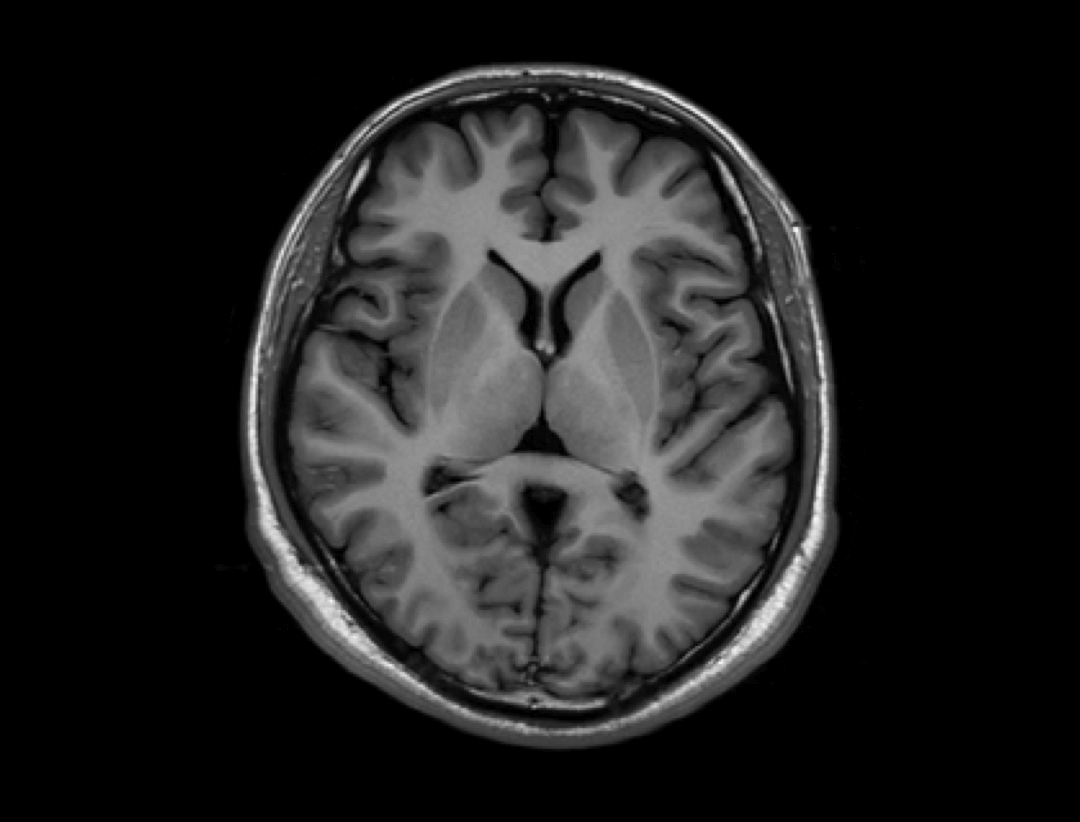

Galerie clinică

Neuro

ARMS